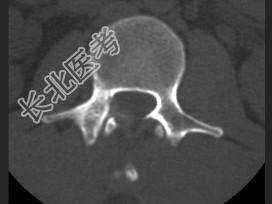

- 单项选择题男,22岁, 腰部疼痛3个月余,结合图像, 最可能的诊断是 ( )

A、腰椎结核

B、动脉瘤样骨囊肿

C、骨肉瘤

D、成骨细胞瘤

E、骨样骨瘤